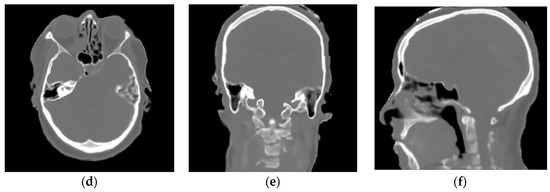

2.2. Magnetic Resonance-Computerized Tomography (MR-CT) Datasets

2.2.1. Training Dataset

2.2.2. Validation Dataset